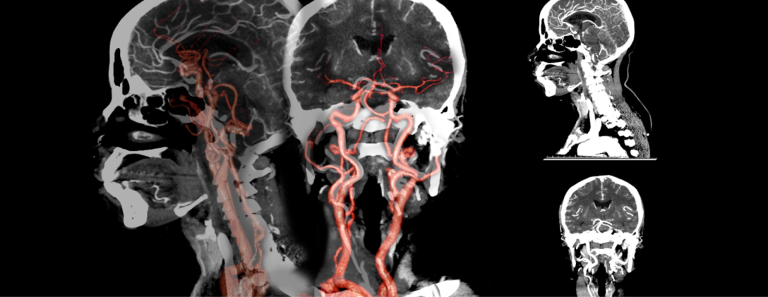

МРТ головного мозку: від пошуку причин мігрені до ранньої діагностики інсульту

Статті Автор: Ан-Сі-Тек Тетяна

Головний біль, запаморочення або раптова слабкість — симптоми, які ми часто списуємо на втому чи погоду. Проте наш мозок — це надскладний «командний центр», який потребує…

Читати →